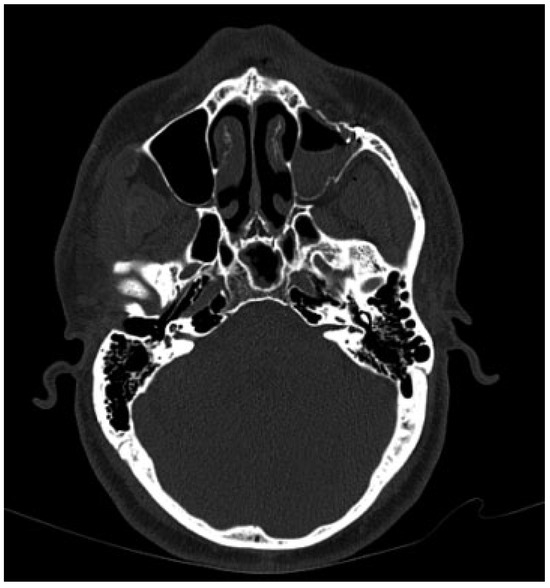

Imaging included a maxillofacial computed tomography (CT) which revealed comminuted fractures of the anterior, posterolateral, and posteromedial walls of the left maxillary sinus with air fluid levels and a hematoma. In addition, fractures of the left orbital roof and lateral and inferior walls were noted. The globes were found to be intact, with no definitive evidence of muscle entrapment. However, disruption of the left superior orbital fissure was found (Figure 3 and Figure 4).

Figure 4. Enhanced view of the left superior orbital fissure from the previous image. Note the constriction and impingement of the superior orbital fissure.